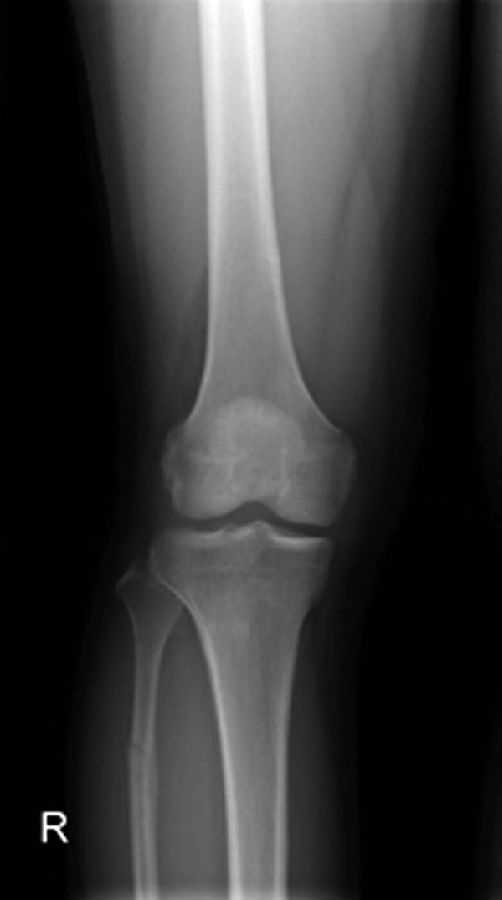

正常髌骨中心点应位于下肢轴线上或稍内侧(图1)。对于髌骨不稳定,膝关节正位像可见髌骨偏离正常的位置,向外侧移位(图2、图3)。

图3 膝关节正位X线成像显示了右膝髌骨偏离正常的解剖位置,明显向外侧移位